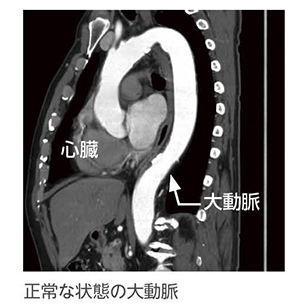

急性大動脈解離は、大動脈壁が中膜レベルで2層に剥離し、動脈走行に沿ってある長さを持ち2腔になった状態と定義されています。動脈壁は、内膜、中膜、外膜の3層構造となっています。内膜に亀裂が生じ、そこから血流が内膜と中膜内に入り、血管が2つ以上に裂けていきます。高血圧に伴う動脈硬化や生まれつき動脈壁の構造異常にある人が起きやすいとされます。

基本的に確定診断できる検査は、造影剤を用いた全身CT検査になります。それ以外の、全身状態や手術前評価としては、頭部CTや心臓エコー検査がありますが、今後の治療方針を決定するのは前述の造影CT検査です。腎機能が低下している場合でも、造影剤使用後の一時透析を視野に入れて検査を行います。

造影剤を用いた全身CT検査を行うことで、急性大動脈解離の裂け目の場所や解離している範囲から分類をして方針を決めていきます。分類にはStanford分類とDeBakey分類があります。また、血管が裂けたことにより、もともとの血管の内腔である真腔と裂けて新しくできた偽腔があり、この偽腔への血流がすぐになくなり、血栓化した場合を早期血栓閉塞と言います。